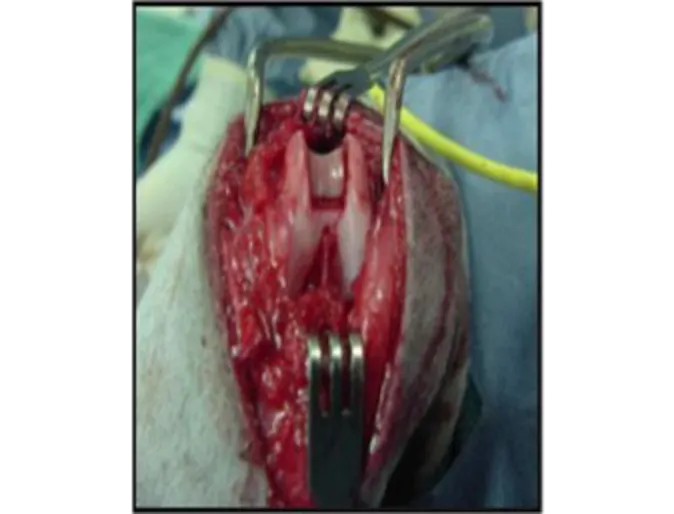

Deepening of the femoral groove is illustrated below. A deeper groove makes it more difficult for the patella luxate.

This figure demonstrates femural groove deepening in a real stifle joint. (Courtesy Dr. Sharon Kerwin, Texas A&M University)